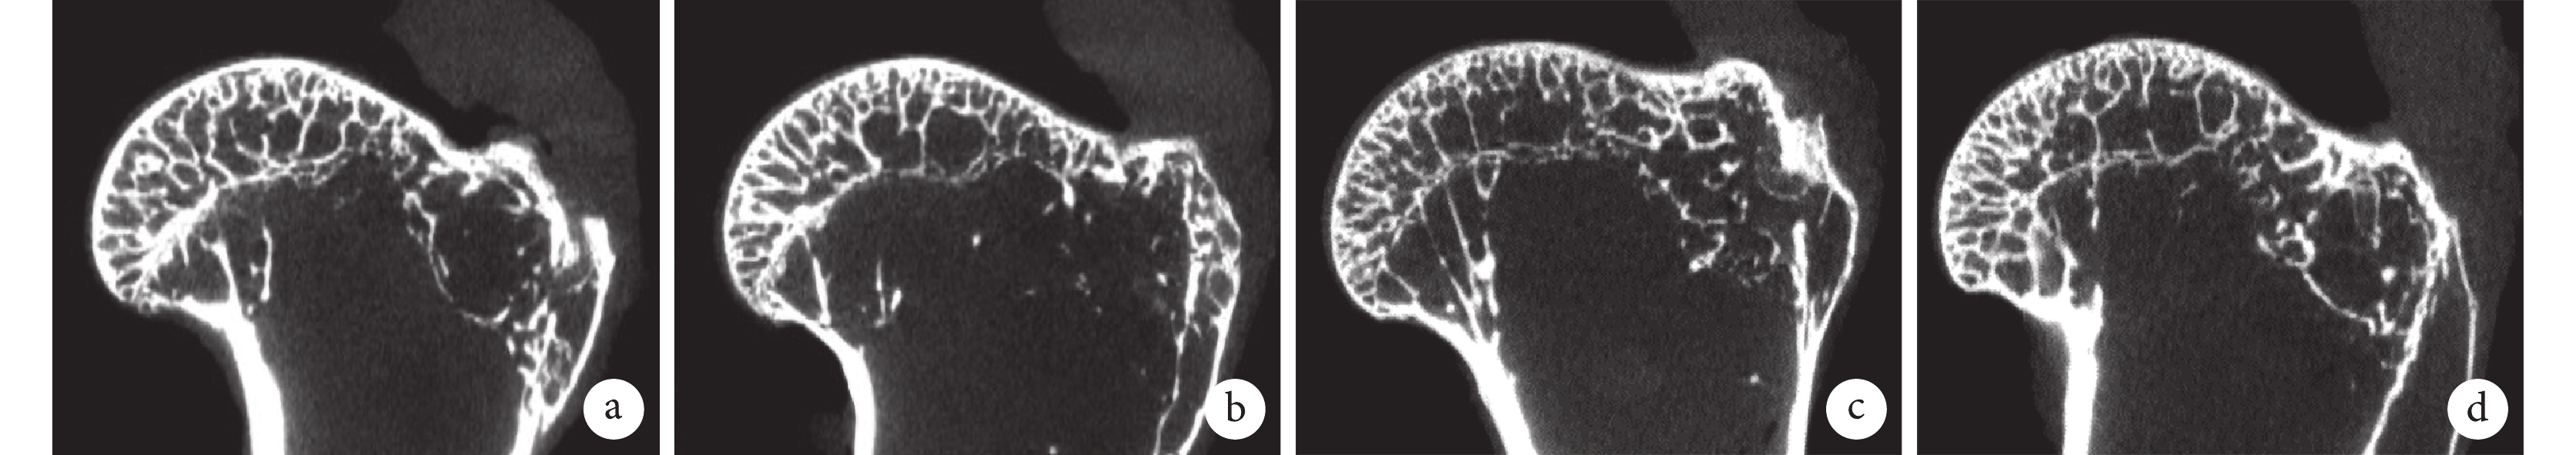

2.4 Micro-CT 檢測

術后 4、8 周,兩組肌腱止點骨床未見明顯差異。見圖 4。術后 4、8 周兩組 TMD、BMD 和 BV/TV 差異均無統計學意義(P>0.05);對照組組內術后 4、8 周 BV/TV 差異有統計學意義(t=5.413,P=0.003),兩組組內其他指標 4、8 周間比較差異均無統計學意義(P>0.05)。見表 1。

a. 對照組術后 4 周;b. 實驗組術后 4 周;c. 對照組術后 8 周;d. 實驗組術后 8 周

Figure4. Micro-CT images of both groups at each time point after operationa. Control group at 4 weeks; b. Experimental group at 4 weeks; c. Control group at 8 weeks; d. Experimental group at 8 weeks